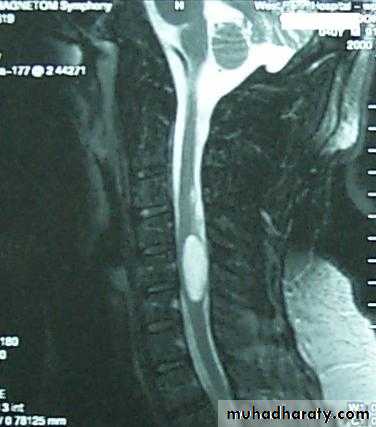

2. CT scan and MRI of the spines will show the lesion clearly.

MRI